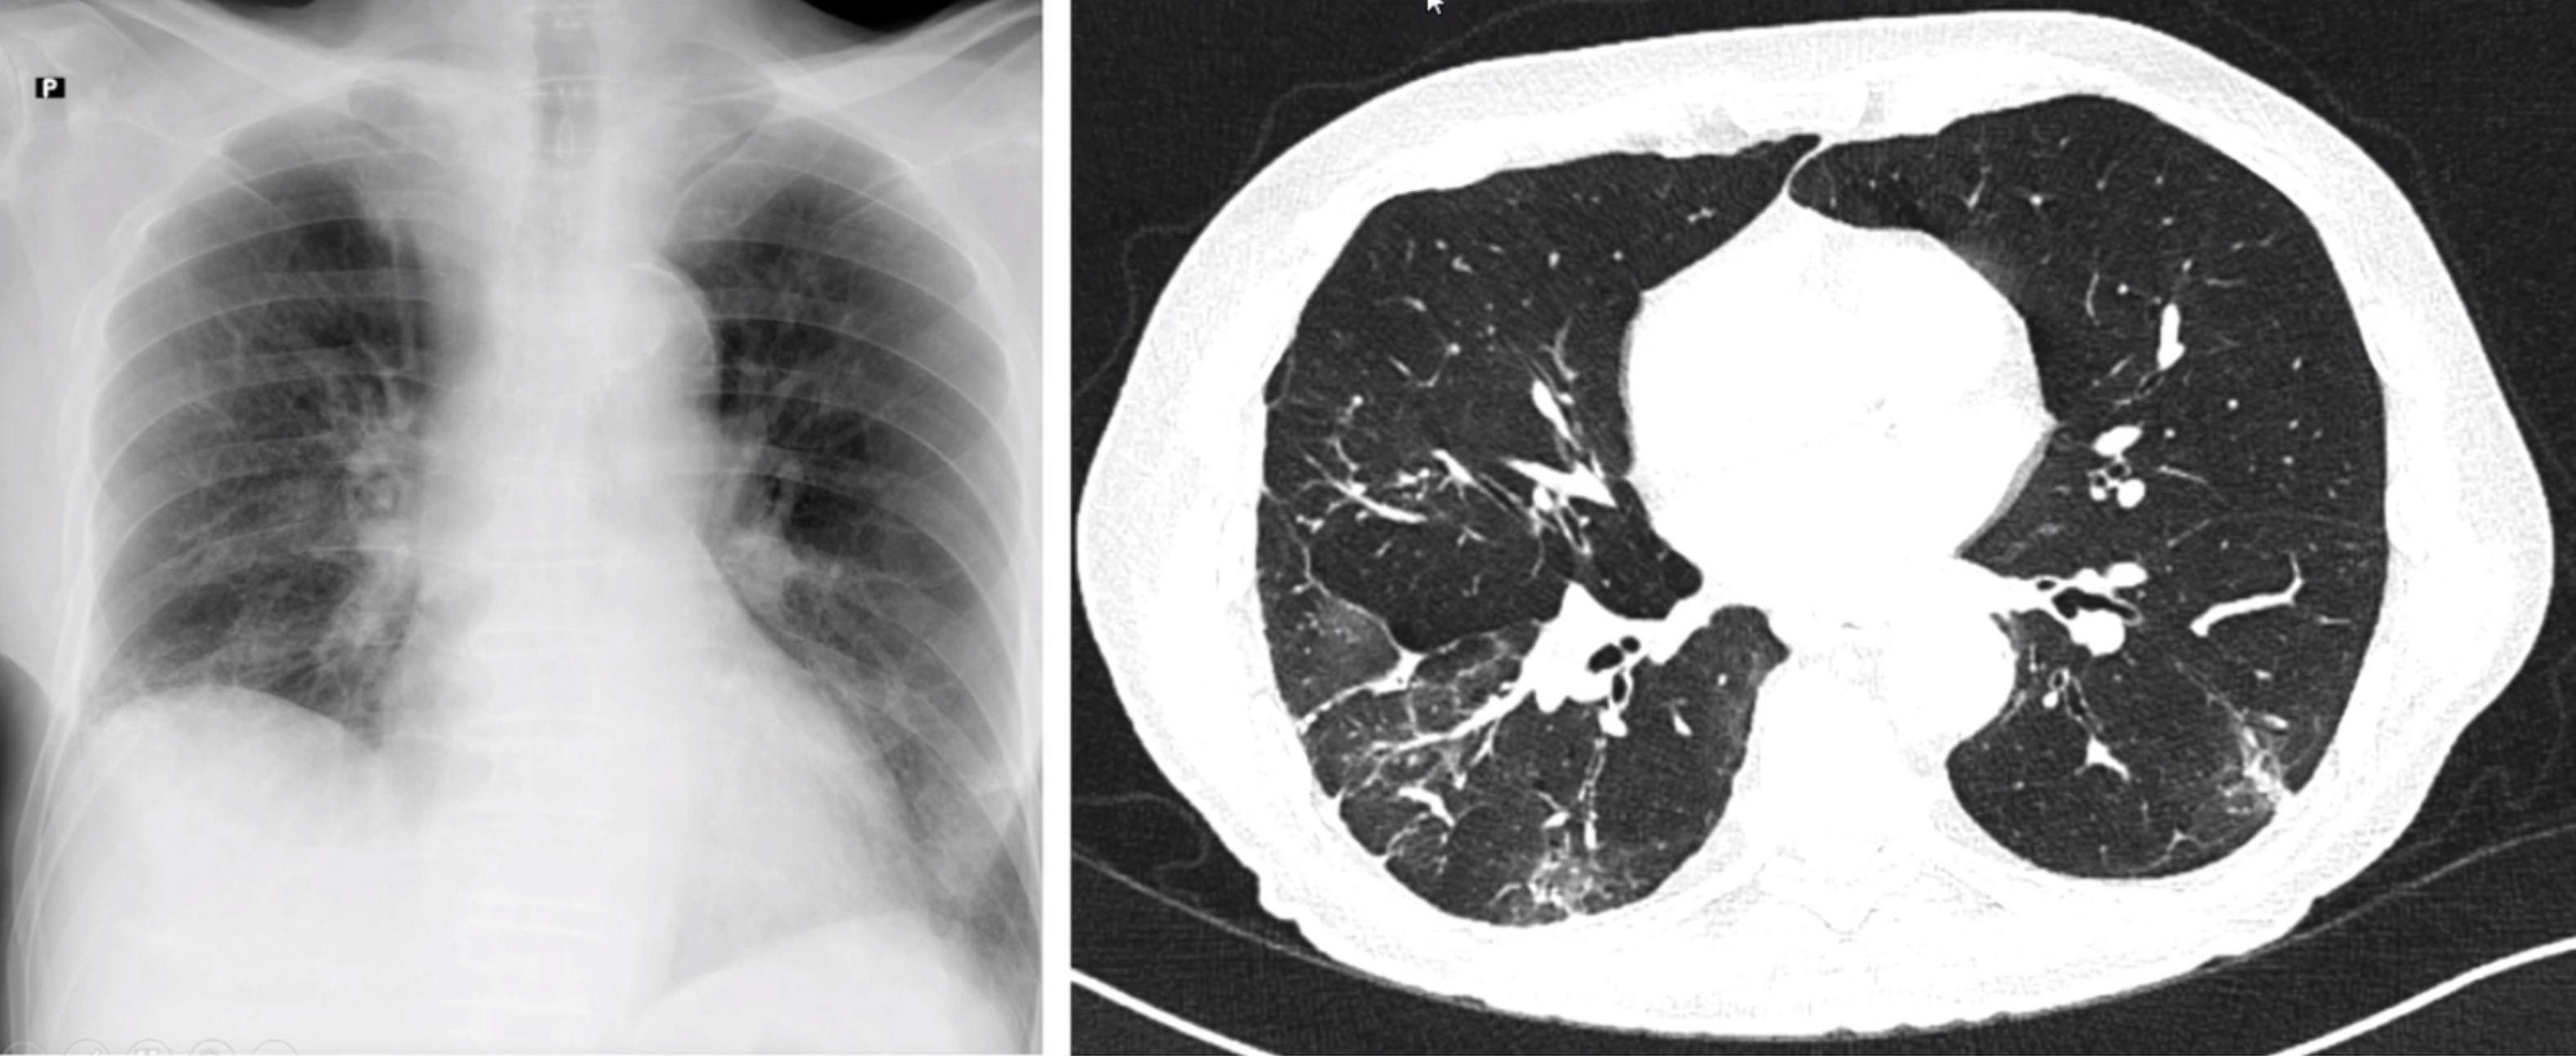

Možnosti rtg diagnostiky

image

Od rentgenového snímku k umělé inteligenci